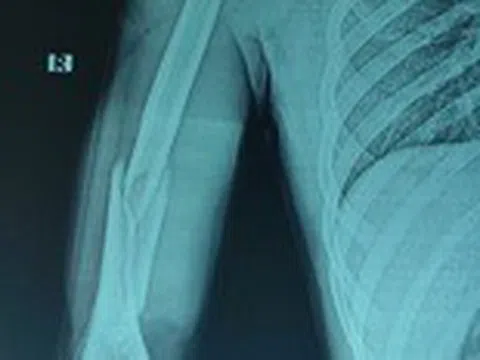

Nam thanh niên tập gym bị gãy xương khi chơi vật tay

Sau khi chơi vật tay cùng bạn, nam thanh niên 21 tuổi nhập viện trong tình trạng cánh tay sưng đau, biến dạng, hạn...